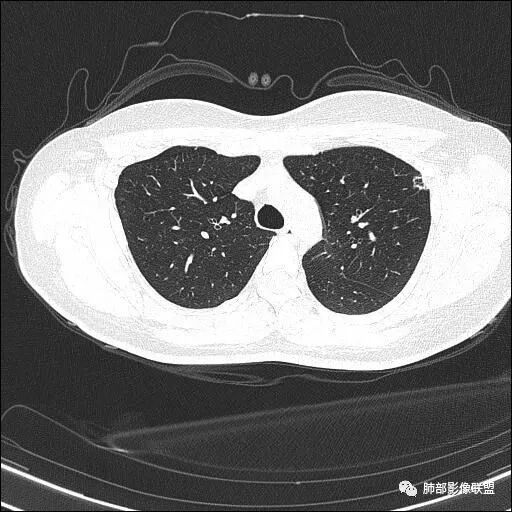

【每日晨读】双肺上叶多发薄壁空洞

双肺上叶多发结节影及纤维索条影,部分结节内部可见空洞形成,形态欠规则,洞壁厚薄均匀,以胸膜下分布为主,多灶性,多态性,临床年轻女性,体检发现,考虑结核,寄生虫?NTM.

双肺上叶尖段分布为主多发囊腔伴斑点,斑片影,囊腔壁不规则,部分内见分隔。考虑结核可能

两肺多发囊或空洞(部分腔内不干净可见间隔影)+多发结节 (右侧胸膜下的结节显著)+左肺尖斑片影。年轻女性,体检发现。考虑结核?鉴别PLCH(奇异囊加结节,吸烟男性多见),转移瘤(要有原发肿瘤病史)

双肺上叶多发结节影,形态不规则,部分结节内部可见空洞形成,洞壁薄,胸膜下分布为主,年轻女性,体检发现,考虑结核

2.双肺多发薄壁空洞影、条索影及结节影,边界较清楚,密度偏高不柔和,散乱,但有成簇倾向或堆积感,胸膜下分布为主,双肺上叶分布为主。

3.空洞相当不规则,缺乏张力,未见血管穿行,未见壁结节,未见液平。

4.双肺门及纵隔未见肿大淋巴结。未见胸腔积液。